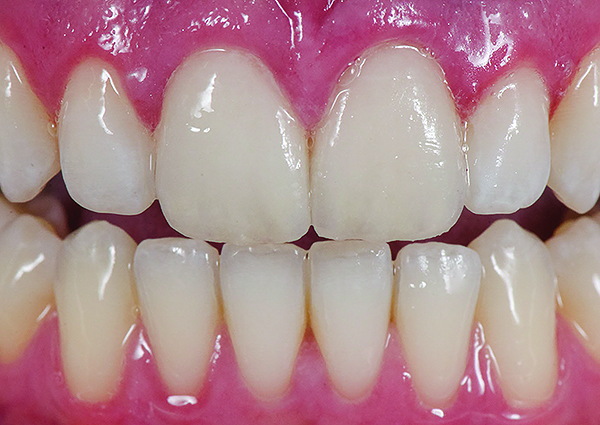

Fig 3. Preoperative (Fig 1), preparation (Fig 2), and final postoperative (Fig 3) images of a two-unit CL-I feldspathic veneer case.

Figure 3